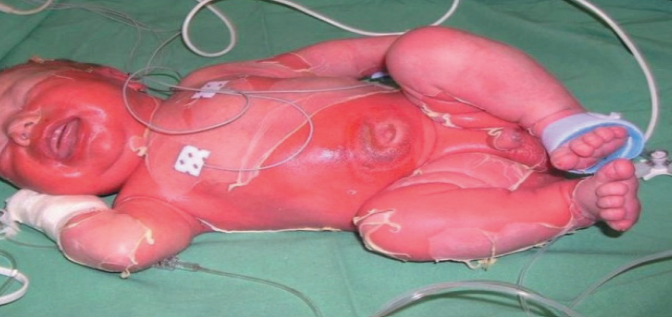

- 9. PEDİATRİK DERMATOLOJİ

9. PEDİATRİK DERMATOLOJİ